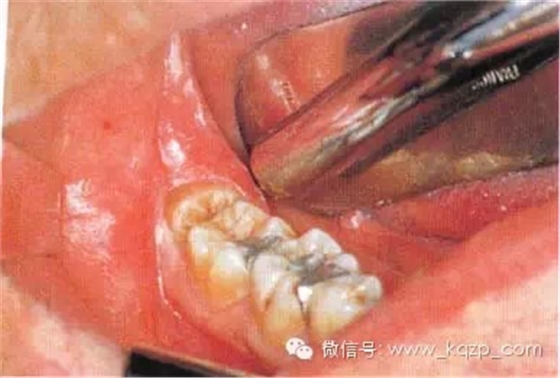

女性患者,40歲。第Ⅰ類,A分類。右下頜第三磨牙阻生,口內(nèi)可見部分牙冠。黏骨膜瓣切口設(shè)計(jì)為:遠(yuǎn)中切口由距離第二磨牙15 mm或更多處開始向前切開,頰側(cè)切口不超過第二磨牙

使用手機(jī)上的圓鉆顯露牙冠最大周徑,遠(yuǎn)中方向顯露至釉牙骨質(zhì)界,頰側(cè)顯露至近中頸部

用縫線穿過舌側(cè)軟組織并將其拉向舌側(cè),以避免其受損并保證術(shù)區(qū)視野清晰。切割牙冠前先將牙根挺松。圖示為用合適的牙挺楔入挺松的牙根下面

盡管事先已挺松牙根,但仍無法順利掏出。于是用紡錘形車針擴(kuò)大牙槽窩,操作時(shí)應(yīng)緊貼牙槽窩內(nèi)壁。拔出牙根后可見根尖肥大。這通常與牙骨質(zhì)增生有關(guān),故不能通過牙挺施以暴力而拔除。免費(fèi)口腔招聘網(wǎng)整理術(shù)者應(yīng)盡量避免折裂牙槽窩骨壁